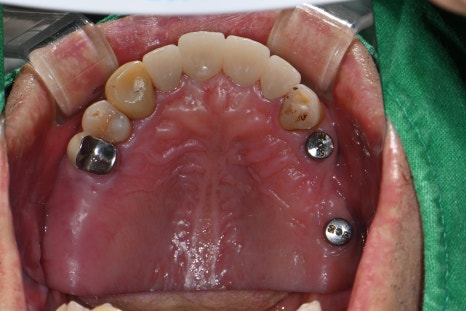

🖼️ Completed molar implant prosthesis photo

Pre-designed implant prosthesis based on a digital scan / The actual intraoral setting

After successfully completing the bone graft and implant,

we precisely fabricated the prosthesis with an oral scanner to restore chewing function.

At Seoul Ob Dental Hospital, all implant prostheses are designed and produced in-house,

allowing us to deliver even better results in terms of precision and customization.